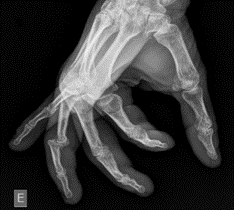

Image 1: Lateral X-ray of the left fourth digit demonstrating a dorsal dislocation at the PIP joint. Case courtesy of Leonardo Lustosa, Radiopaedia.org, rID: 99559

Image 2: Magnification of the X-ray above demonstrates an avulsion fracture of the base of the phalanx, indicating a volar plate avulsion fracture. Case courtesy of Leonardo Lustosa, Radiopaedia.org, rID: 99559